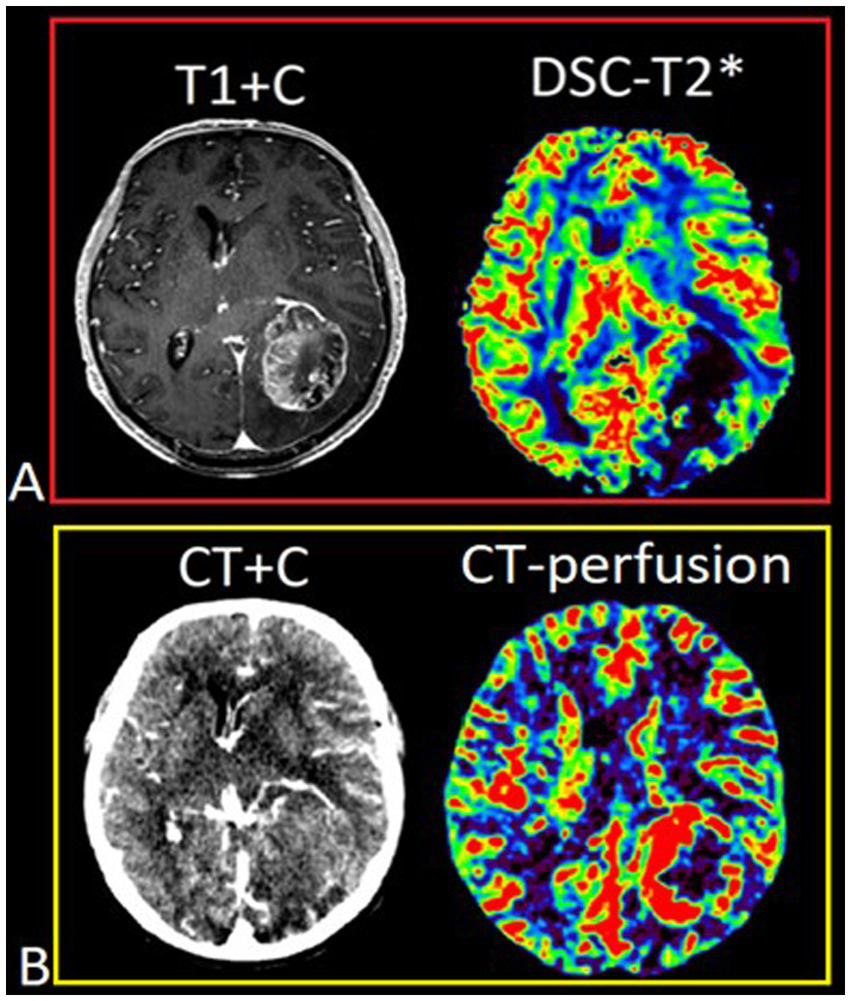

DSC-T2* perfusion was performed in all 74 patients and additional CT perfusion was carried out in 23 of 74 patients. The limitations associated with artifacts from blood degradation products are shown in Figure 2.

Figure 2

Patient T., 42 y.o., left occipital lobe glioblastoma. (A) Post-contrast T1 WI and DSC-T2* perfusion. DSC-T2* perfusion demonstrates marked magnetic susceptibility artifacts with local signal loss due to blood degradation products. (В) CT with contrast (arterial phase) and CT-perfusion. CT-perfusion does not contain any artifacts and fully displays the tumor boundaries.